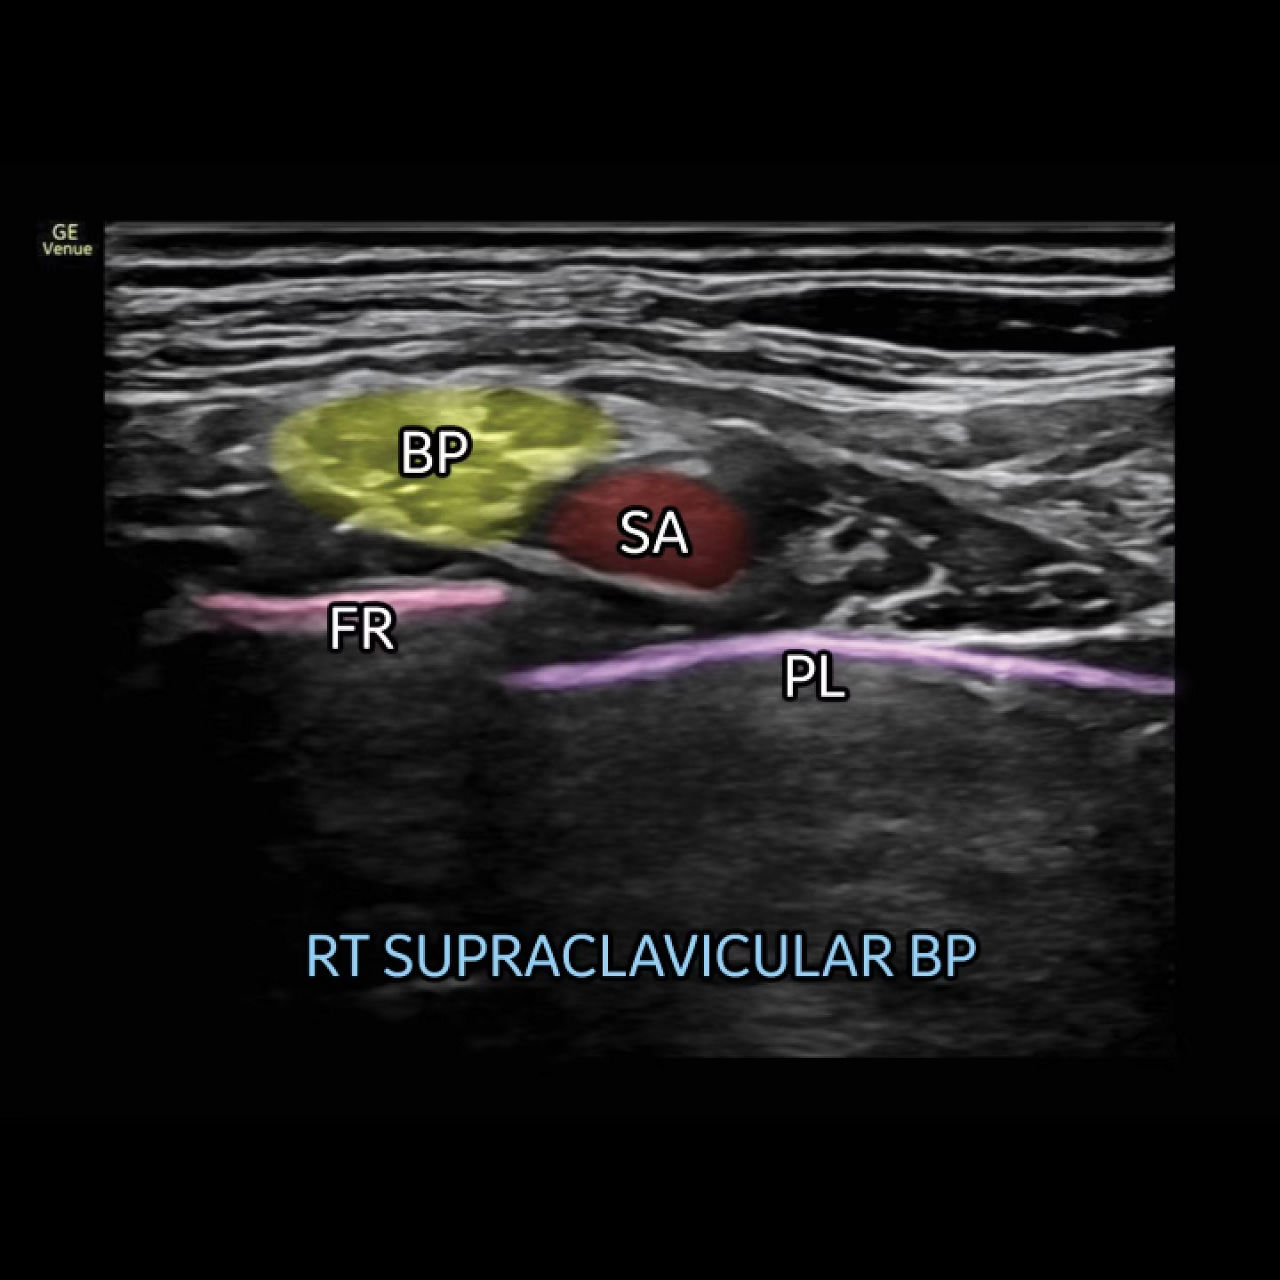

Perform ultrasound-guided peripheral nerve blocks with Nerveblox™

Standard for Venue and Venue Go, this AI-enabled tool automatically labels key anatomical landmarks in the ultrasound image, helping clinicians feel confident during the procedure and streamlining the workflow with the goal of reducing procedure time.